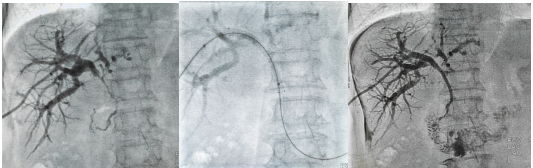

在胡育斌主任医师带领下,医师团队首先实施“超声联合DSA引导PTCD术”置入胆道引流管快速退黄,后复查胆道造影准确判断右肝管、肝总管及胆总管上段狭窄,并精准测量狭窄的长度,制定胆道支架植入策略。经过充分准备后,成功为患者实施胆道支架植入术。目前,该患者已康复出院。